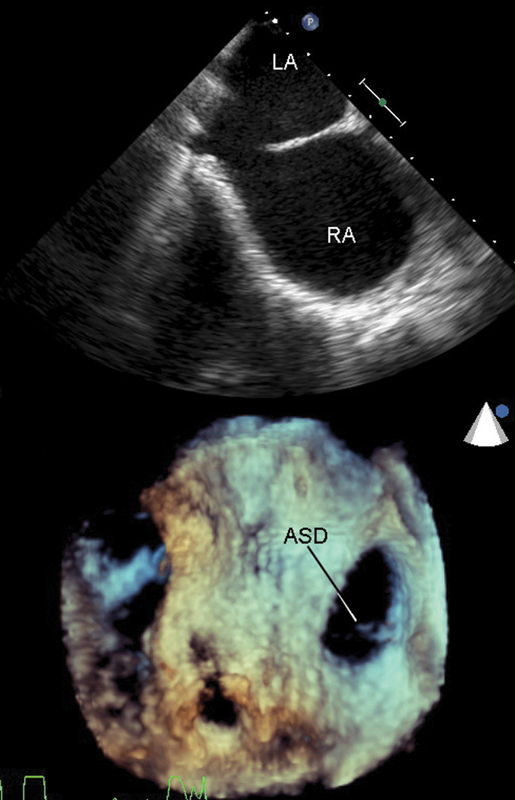

فحوصات تشخيصية لبعض امراض القلب والشرايين التاجية